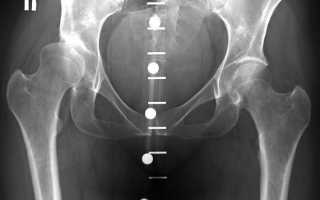

Диагноз «диспластический коксартроз тазобедренного сустава» устанавливается на основе клинического обследования пациента и дополнительных диагностических методов. С помощью инструментального обследования можно определить степень прогрессирования заболевания и выбрать оптимальную стратегию лечения (вопрос решается о консервативной терапии или хирургическом вмешательстве). Обычно для диагностики достаточно провести ультразвуковое исследование и рентгенографию тазобедренного сустава.

С помощью этих диагностических методов необходимо выяснить:

- Степень смещения головки бедра относительно вертлужной впадины;

- Угол наклона вертлужной впадины;

- Наличие деформаций и уплощения вертлужной впадины;

- Измерить патологическое увеличение шеечно-диафизарного угла;

- Степень выраженности коксартроза.

Для подтверждения клинического диагноза требуется провести ряд лабораторных исследований. У пациентов с диспластическим коксартрозом в биохимическом анализе крови наблюдается повышение скорости оседания эритроцитов (СОЭ), уровня серомукоида и глобулинов. В тяжелых случаях заболевания для более детального изучения тазобедренного сустава может потребоваться выполнение компьютерной томографии и магнитно-резонансной томографии.